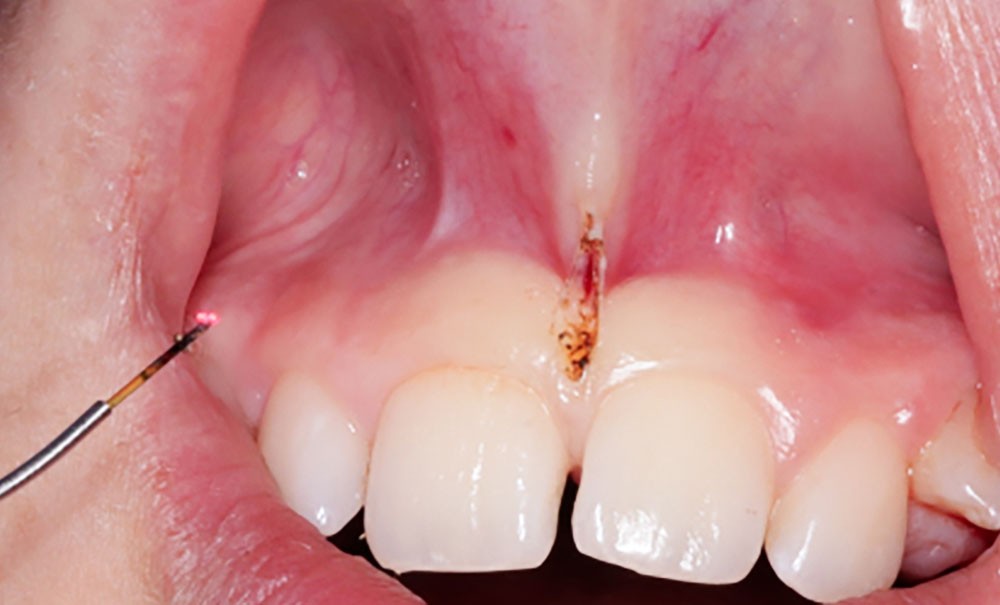

Frénectomie labiale au laser diode chez l’adolescent

Dans notre pratique orthodontique, le frein interincisif peut représenter une anomalie anatomique de la gencive et/ou de la muqueuse alvéolaire. Pour cette raison, l’élimination partielle ou totale peut trouver son indication [1].

Cependant, dans certains cas de frein à insertion basse dans la gencive attachée avec mobilisation accrue de la gencive marginale et risque pour l’attache épithéliale, et/ou avec une épaisseur de tissu importante, il est recommandé de le supprimer. Cette suppression…